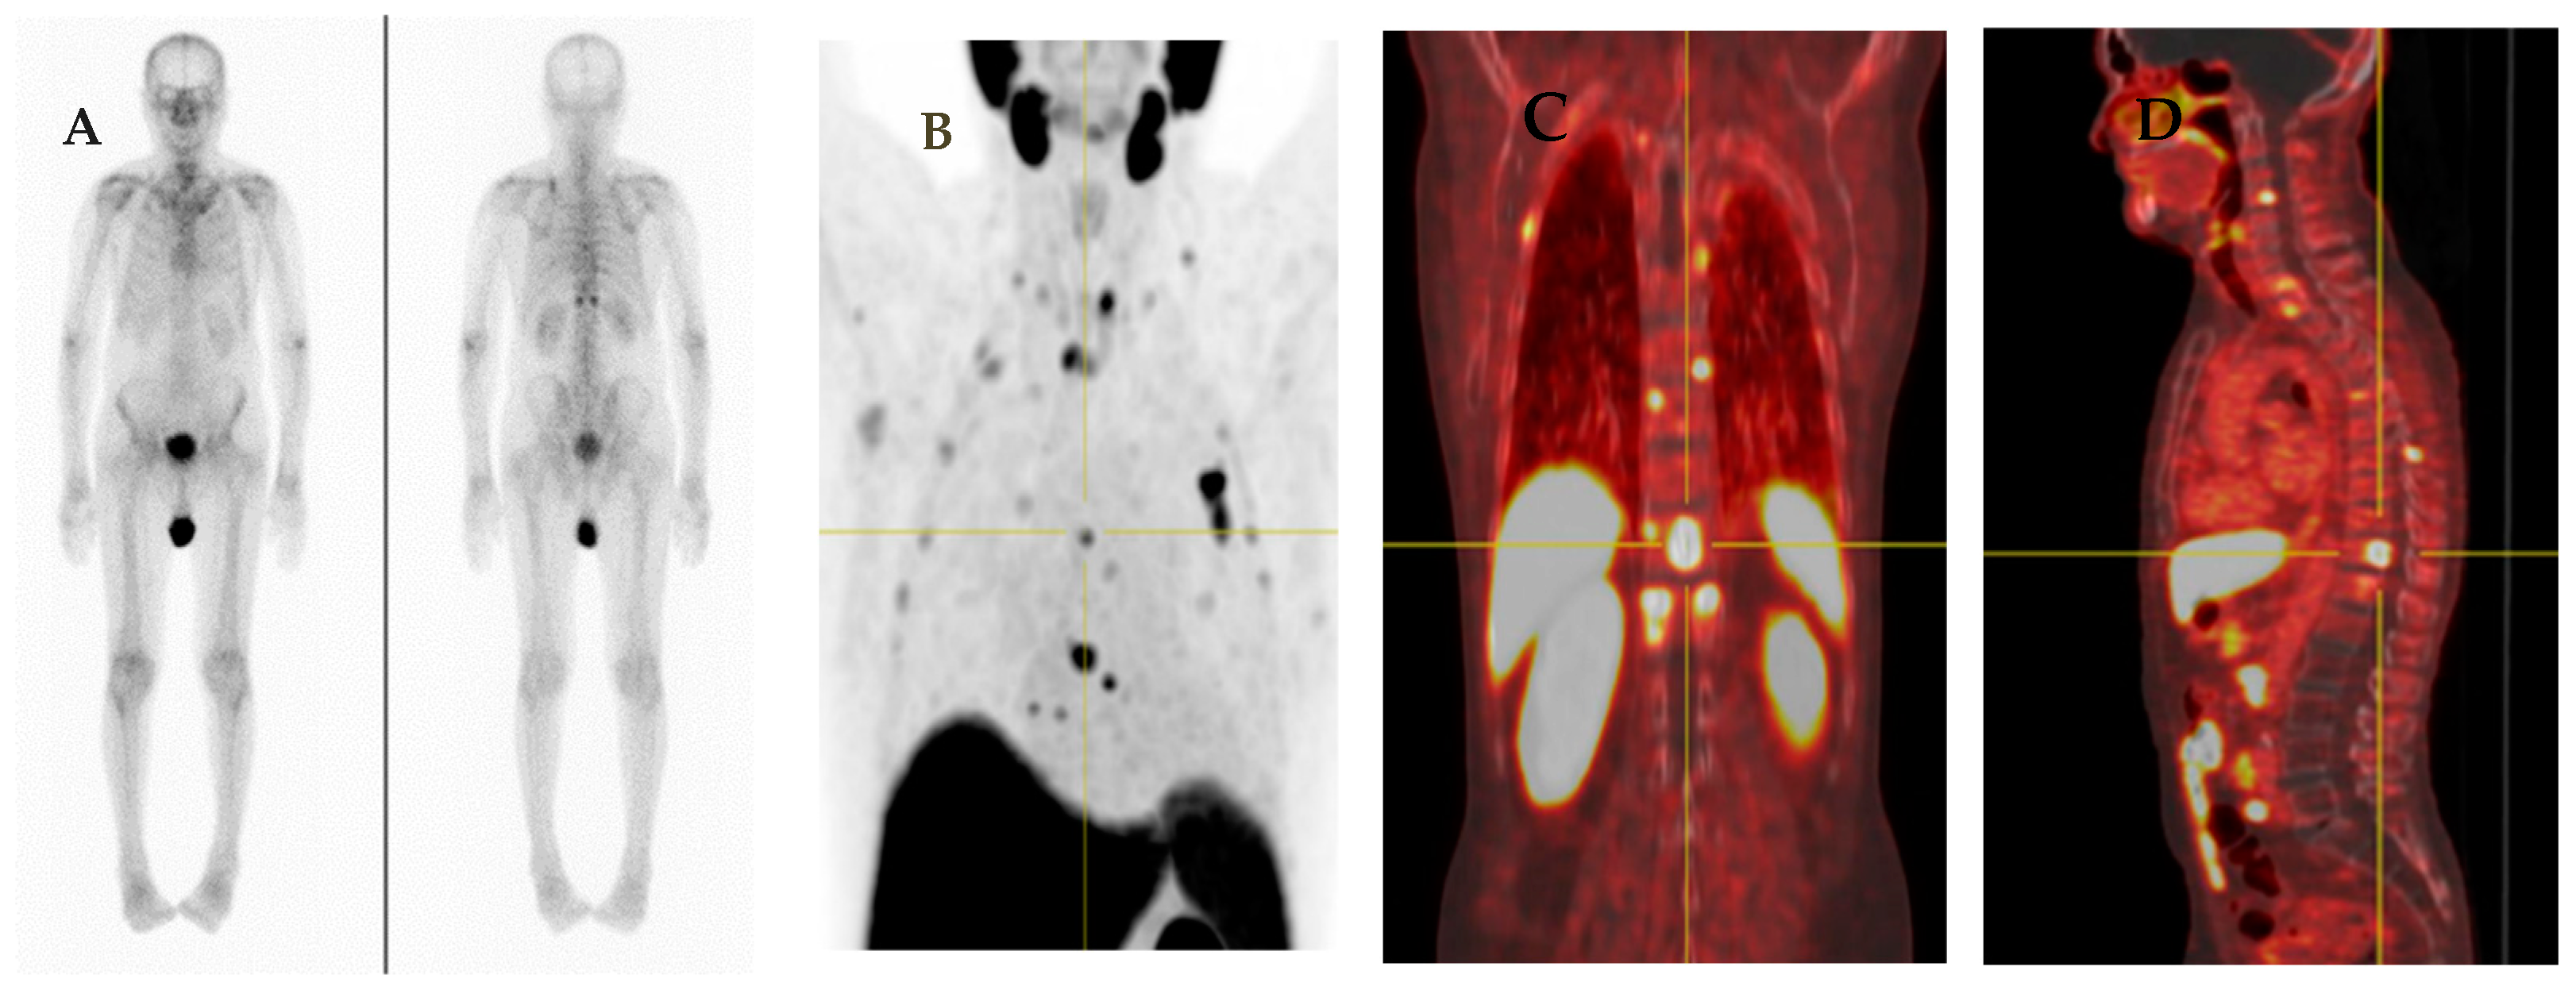

Following radical treatment for PCa with either external beam RT (EBRT) or radical prostatectomy (RP), between 27 and 53% of patients experience BCR [75]. There are differences in BCR definitions between and within the main curative contexts. According to the recent EAU guidelines on PCa, the threshold for best predicting further metastases after RP is PSA > 0.4 ng/mL and higher [76,77,78]. Prospective studies have reported the advantages of PSMA-targeted imaging in BCR in acquiring useful clinical information that could eventually change therapeutic strategies [69,79,80]. Various international guidelines recommend PSMA-PET imaging to be considered to clarify equivocal findings, especially if the results will directly and immediately influence therapeutic decisions (Figure 2).

Figure 2.

A 74-year-old man with adenocarcinoma of prostate gland (Gleason score 5 + 4 = 9) S/P radical prostatectomy with bilateral orchidectomy, developed rising serum PSA with level of 1.2 ng/mL which was suspected of BCR. His bone scan revealed equivocal lesions at left scapula, T8, and 12 vertebrae (A). He also performed 18F-PSMA PET/CT for evaluating BCR. There are multiple PSMA-avid lesions on MIP image (B) associated with multiple PSMA-avid mixed osteolytic and blastic metastases at multiple levels of vertebrae, both scapulae and multiple bilateral ribs as seen on coronal PET (C) and sagittal PET (D) images.